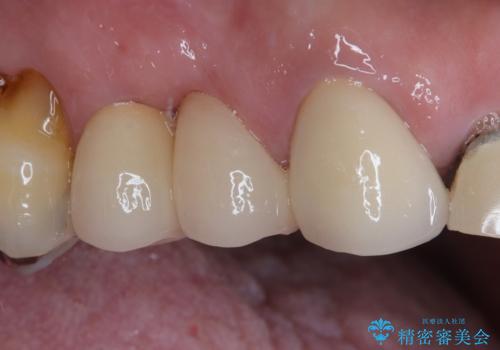

以前矯正治療をされ、その時には歯列が整ったので満足されたそうですが、若干の後戻りにより隙間ができ、矯正治療前に治療していた虫歯の跡が気になったため、オールセラミックによる審美治療を希望されました。

目立つ範囲である前歯4歯をオールセラミッククラウンにて補綴することとしました。